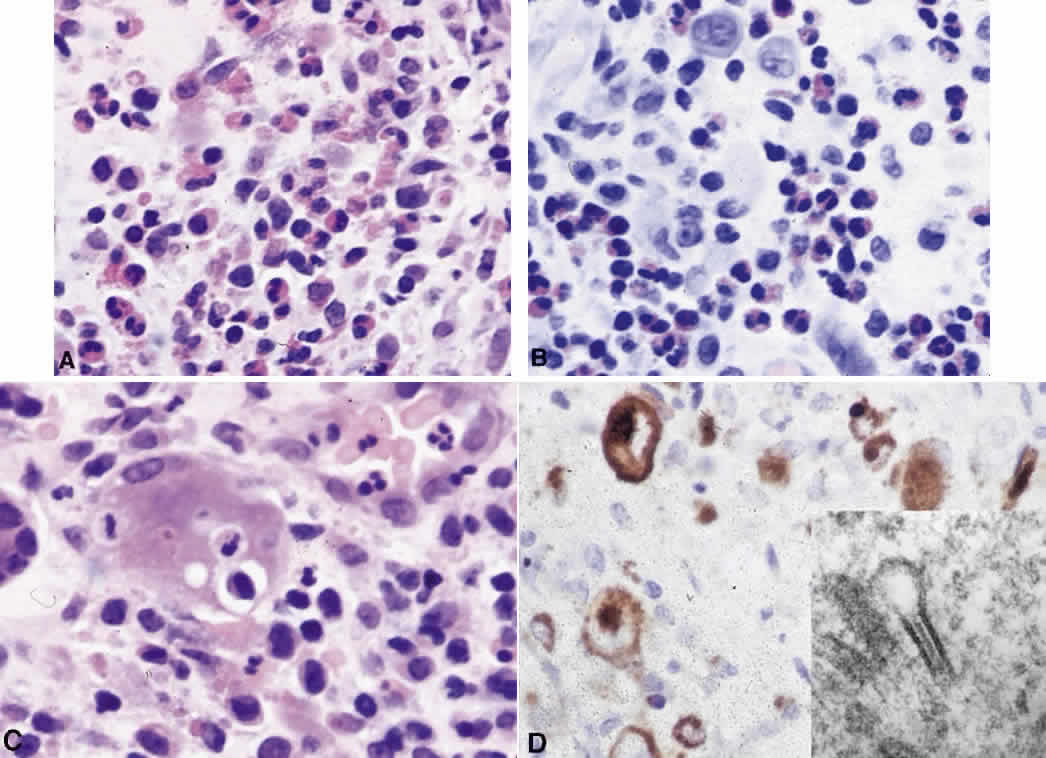

Systemic non-Hodgkin's lymphomas usually present with painless lymph node enlargement in one or more nodes. Adults usually are in their fifth or sixth decade, and presentation in childhood is extremely rare. The fever, night sweats, and weight loss characteristic of Hodgkin's disease generally are absent. Splenomegaly may develop in 20% of patients. Patients usually have normal blood counts, although they may develop lymphocytosis, especially with well-differentiated lymphocytic lymphomas, or pancytopenia with anemia, hemorrhage, petechiae, ecchymosis, and infection—the pancytopenia occurring in one third of patients as a result of bone marrow involvement or chemotherapy and radiation. Patients with B-cell lymphomas tend to develop difficulty with bacterial infection, whereas those with T-cell lymphoma may develop difficulty with delayed-type hypersensitivity and viral infections. Leukemic conversion is rare in adults, although it occurs in 25% of children. In children, an acute leukemic phase may be the initial presentation. Furthermore, children are more likely to develop extranodal and aggressive disease, although they may respond well to therapy.50 In a series of 1269 patients, of whom only 3 (0.42%) presented initially with proptosis, one third of patients presented with extranodal disease and a few with bone marrow invasion.51 There was a 1.3% incidence rate of orbital disease secondary to systemic lymphoma.